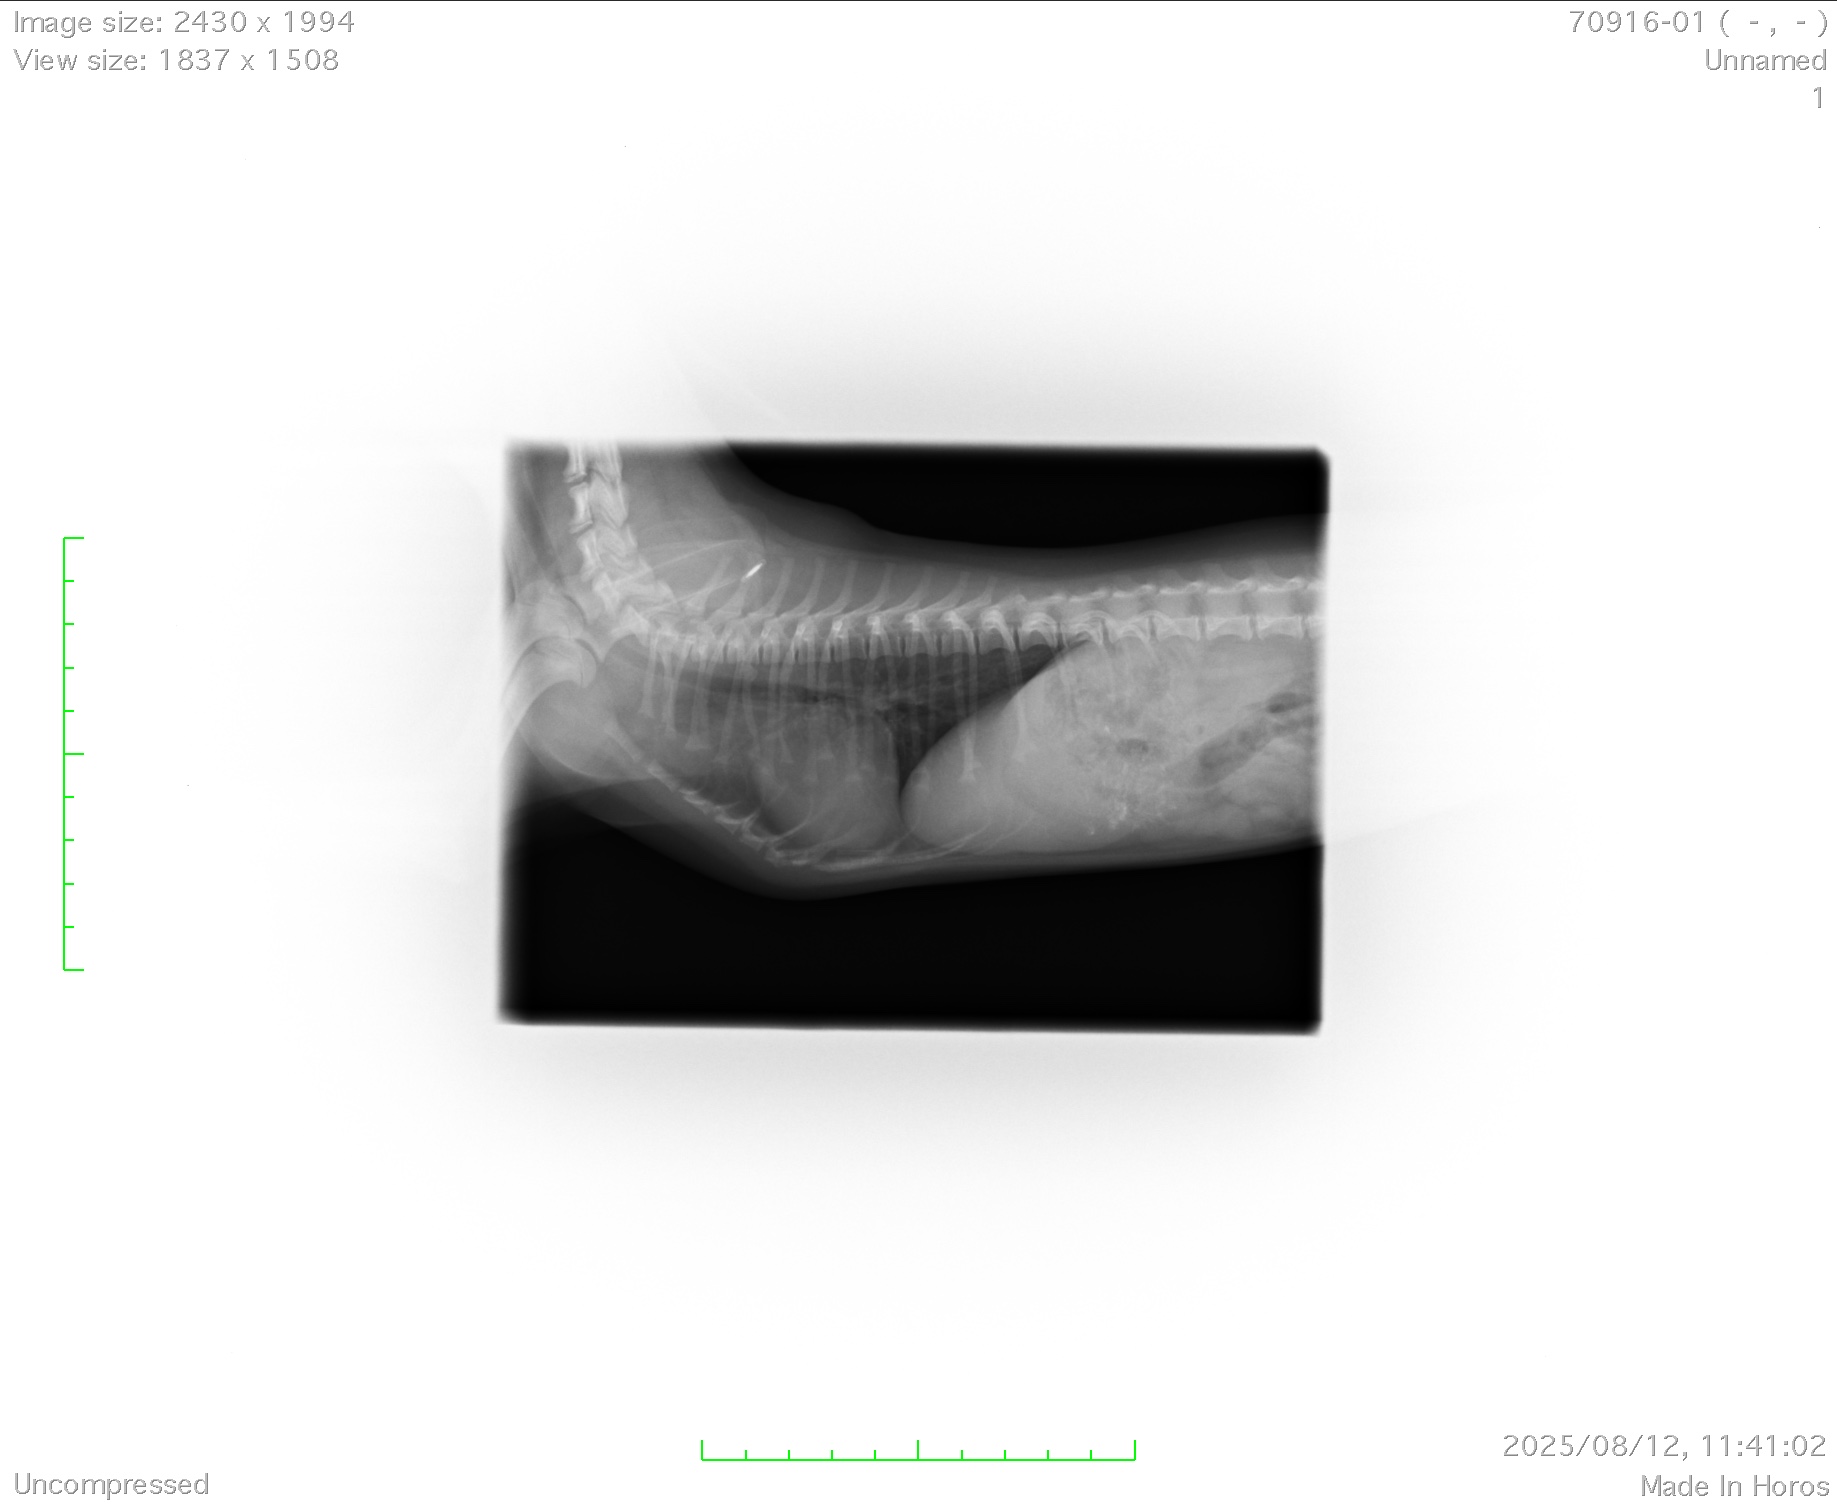

今回は体重がなんと600gと小さいため通常の動物病院では手術はおろか、「開胸」するという大掛かりでリスクの高い手術はほとんどできないと思います。しかし当グループには、体重が小さくても麻酔ができる麻酔の専門家、600g以下でも開胸ができるスペシャルなテクニックを持ったドクターが在籍しており、一般的な動脈管の手術死亡率5〜10%と言われる難易度の手術ですが、現在死亡率0%を維持できております。

無事手術は終わり、今では元気になって苦しかった症状は全く出ない状況になりました。これからは幸せな犬生が待っていることでしょう。